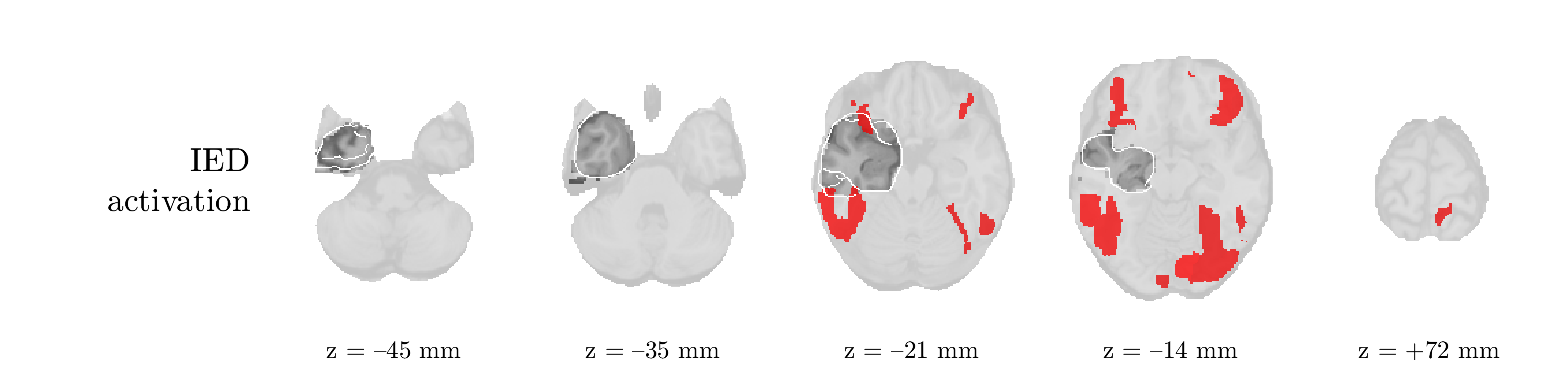

Patient 2

We analyze the solution with sources, and show the results in Figure 3 and 4. As for patient 1, we found a source which is strongly correlated to the MWF envelope, and which had a mostly low-frequency behavior characteristic for spikes. The topography is mostly uninformative, and does not clearly correspond to the patient’s clinical data. The third source is mostly present at both sides of the head, is very sparsely active in time, and has a high-frequency content: this is most likely an artifact due to the neck muscles. Again, there is one of the highest-entropy HRFs which belongs to a ROI in the IOZ. Now, the waveform is clearly resolved from the other HRFs, through the strong initial dip (before 0 seconds). Such a dip is sometimes observed in HRFs, but its underlying physiological mechanism is not yet fully understood. It is possible that this dip reflects altered vascular autoregulation near the IOZ (cfr. the explanation in the Section 1 of the main text), or a rapid depletion in oxygen due to IED generation (before the IED becomes visible on the EEG). Figure 4 furthermore shows that the IED-related component is significantly active in parts of the IOZ, and deactive in others. As mentioned earlier, this deactivation may or may not be due to errors in sign correction. Interestingly, the ROI with the high alteration in neurovascular coupling is distinct from both the activated and deactivated ROIs.